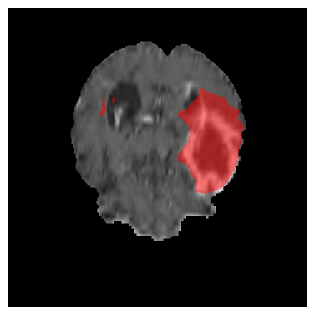

Appendix A Qualitative results

Figure 5 illustrates the segmentation evolution for the same BRATS patient in S2 sequence. The key difference here is that the best buffer-free strategy is EWC (=1), and training on BRATS data starts from episode 2 instead of episode 1 as BRATS is encountered at episode 2 in S2. The cumulative approach retains segmentation across episodes but continues to generate false positives, which become even more pronounced in the final episode. The naive approach, lacking a CL mechanisms, completely overrides previous knowledge, leading to failed segmentation in later episodes. EWC (=1) approach initially maintains segmentation but experiences a sharp decline in episode 4, where it fails to segment the tumor. In the final episode, it undersegments the lesion, missing a significant portion of the tumor. In contrast, the proposed approach consistently preserves segmentation across episodes. While initially introducing false positives, it gradually refines predictions, retaining the tumor region while minimizing misclassifications. It maintains clear tumor delineation by the final episode, demonstrating effective knowledge retention and adaptability throughout training.